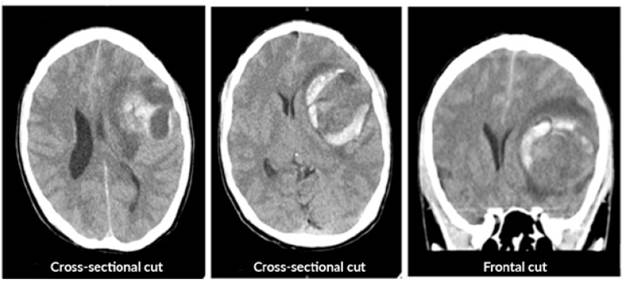

An emergency craniotomy for drainage was scheduled based on the results of the CT scan. Craniotomy showed a yellowish, hard tumor mass with necrosis and suggestive of astrocytoma. The patient did not require antibiotic management after the procedure and a new CT scan was requested, which showed satisfactory tumor resection with residual perilesional edema, without deviation from the midline (Figure 2). The histopathological study described resection compatible with glioblastoma (Figure 3).

Simple computed tomography of the brain after surgery.

Figure 2: Simple computed tomography of the brain after surgery.

Source: Document obtained during the study.